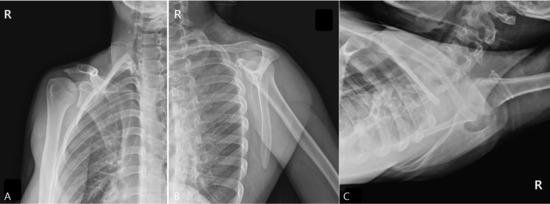

Radiographs, including true anteroposterior, Y, and axillary views, showed no abnormality [Figure 1], but the MSK ultrasound revealed cortical irregularity in the right scapular body, corresponding to the site of pain. Two distinct longitudinal views were obtained: one directly over the medial scapular border showing a subtle cortical irregularity, and another medial to the border revealing a more extensive cortical disruption with a longer fracture line [Figure 2]. Sonoguided digital palpation was performed, and localized tenderness was observed at the site of cortical irregularity, leading to a provisional diagnosis of scapular fracture. The chronological sequence of clinical events, diagnostic imaging, and interventions is summarized in Table 1. Following the suspicion of a scapular fracture, treatment focused on both potential fracture healing and the restoration of scapular stability [21]. Prolotherapy injections were administered to the right scapular medial border and surrounding ligaments to promote structural stability. Prolotherapy was administered using a solution of 10% dextrose. Under ultrasound guidance, approximately 5 mL of the solution was injected into the periosteum and surrounding tendons at the site of cortical irregularity on the medial scapular border. This procedure was repeated bi-weekly for a total of 4 sessions over two months.

Figure 1. Plain Radiographs of the Right Scapula. These radiographs were taken due to the worsening of wrist symptoms, accompanied by a feeling of instability in the scapular region. (A) True anteroposterior (AP) view of the shoulder, (B) scapular Y-view, and (C) axillary view. All views showed no evidence of a definite fracture line, dislocation, or other specific abnormalities.